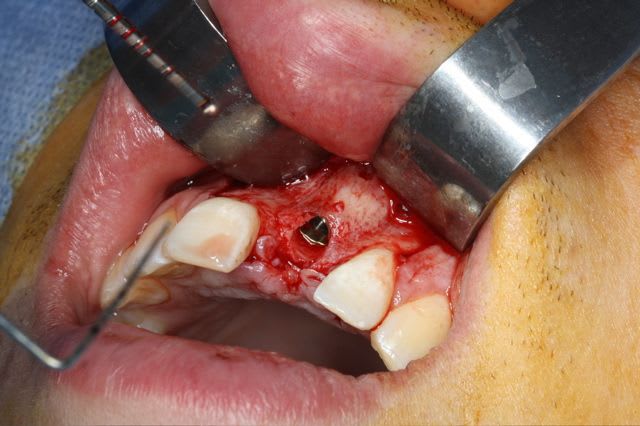

greffe onaly,

dépose des vis et pose de l'implant à 5mois1/2 avec un cj roulé et mise en place de la vis de cica,

pour la greffe: un lit de copeaux généreux et un bloc corticale par dessus et des copeaux pour boucher les espaces. Pas de membrane par dessus, seulement le périoste.